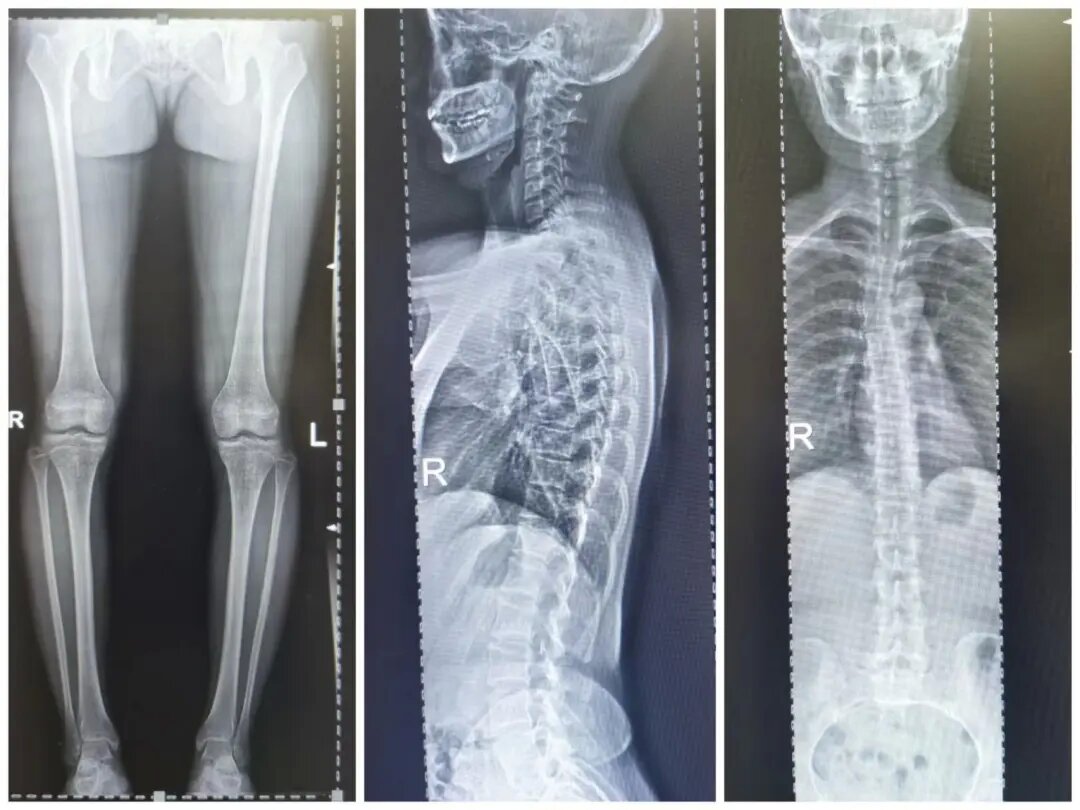

四、脊柱全長攝影及雙下肢全長攝影

對脊柱側(cè)彎、髖關(guān)節(jié)置換、膝關(guān)節(jié)置換給予全面、直觀的影像資料。